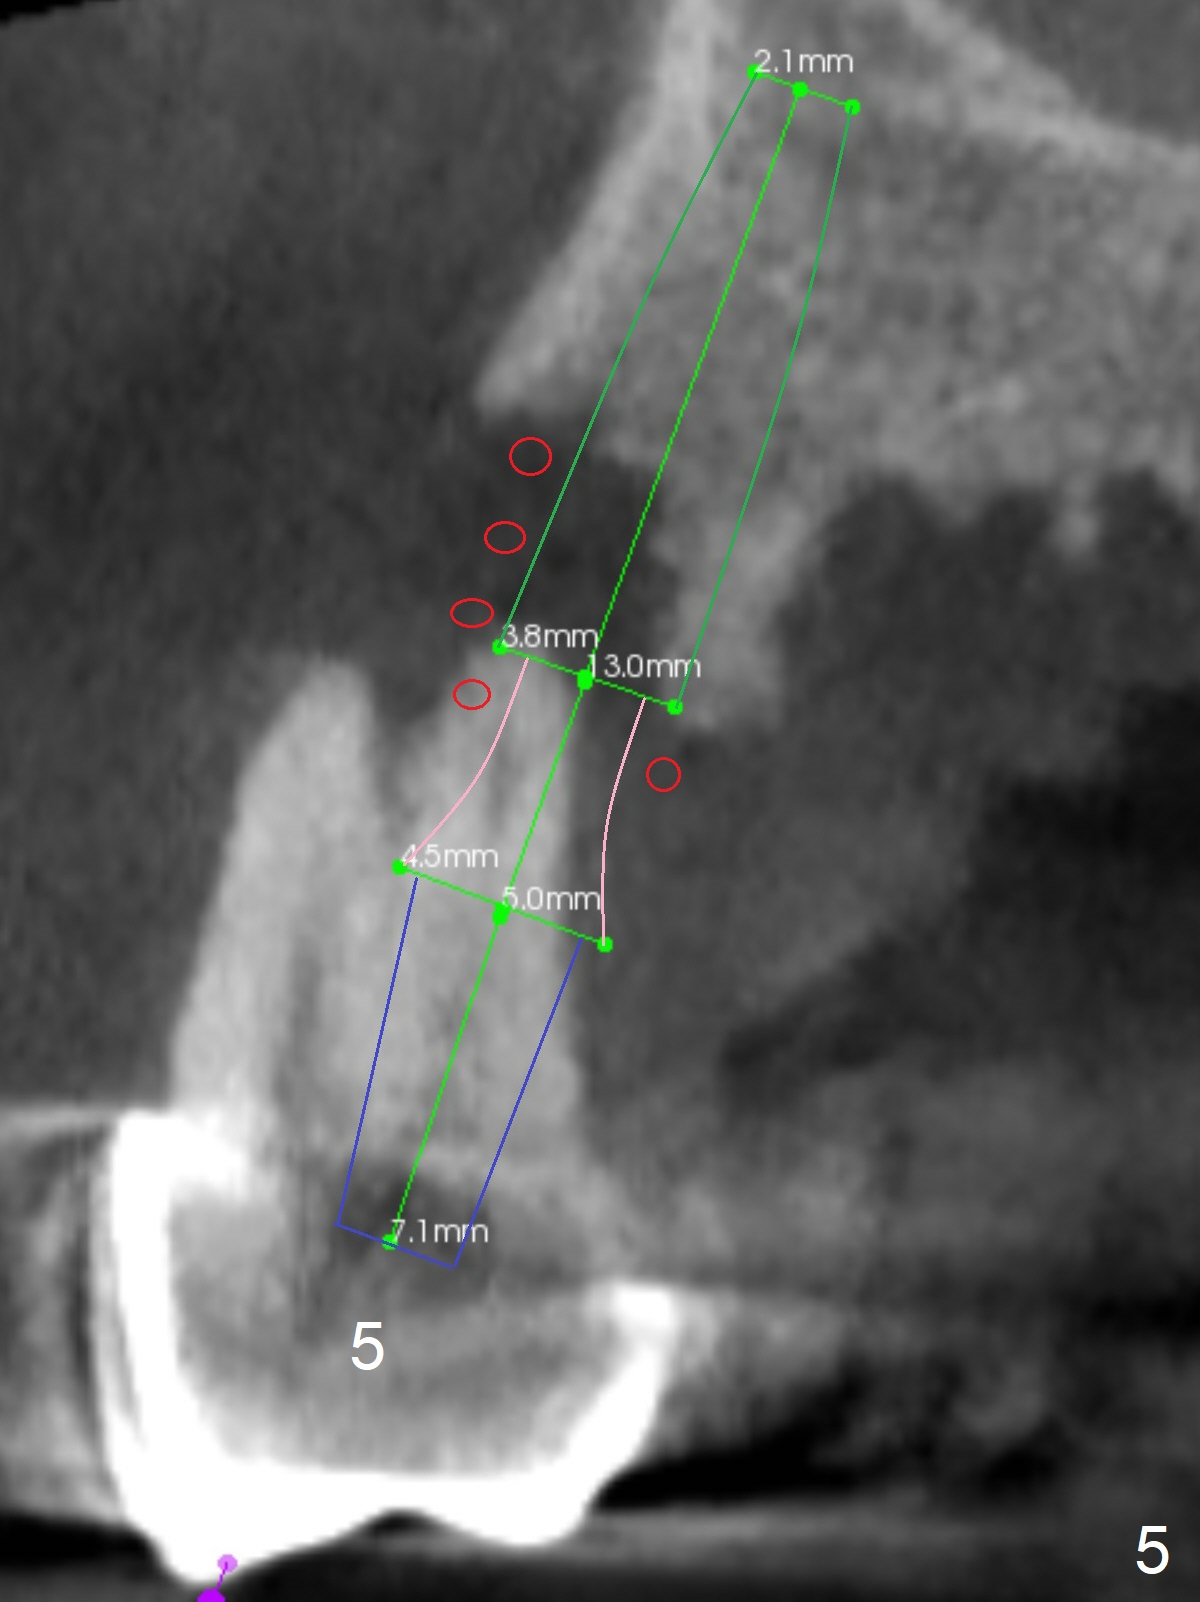

A 45-year-old man will return for #2, 3 and 5 extraction and implants (Fig.1,2). Take PAs for and Reline #7,9,11 provisional crowns and fabricate #11-13 temporary FPD if #15 implant is still unstable (5 months postop). Establish normal occlusal contact.

Extract #2 or remove #3-5 FPD first whichever is looser. Use the other as reference guide. Place Osteogen plug in the palatal socket of #2 ad 3 (Fig.3,4 yellow box) and allograft around the implants (red circles).